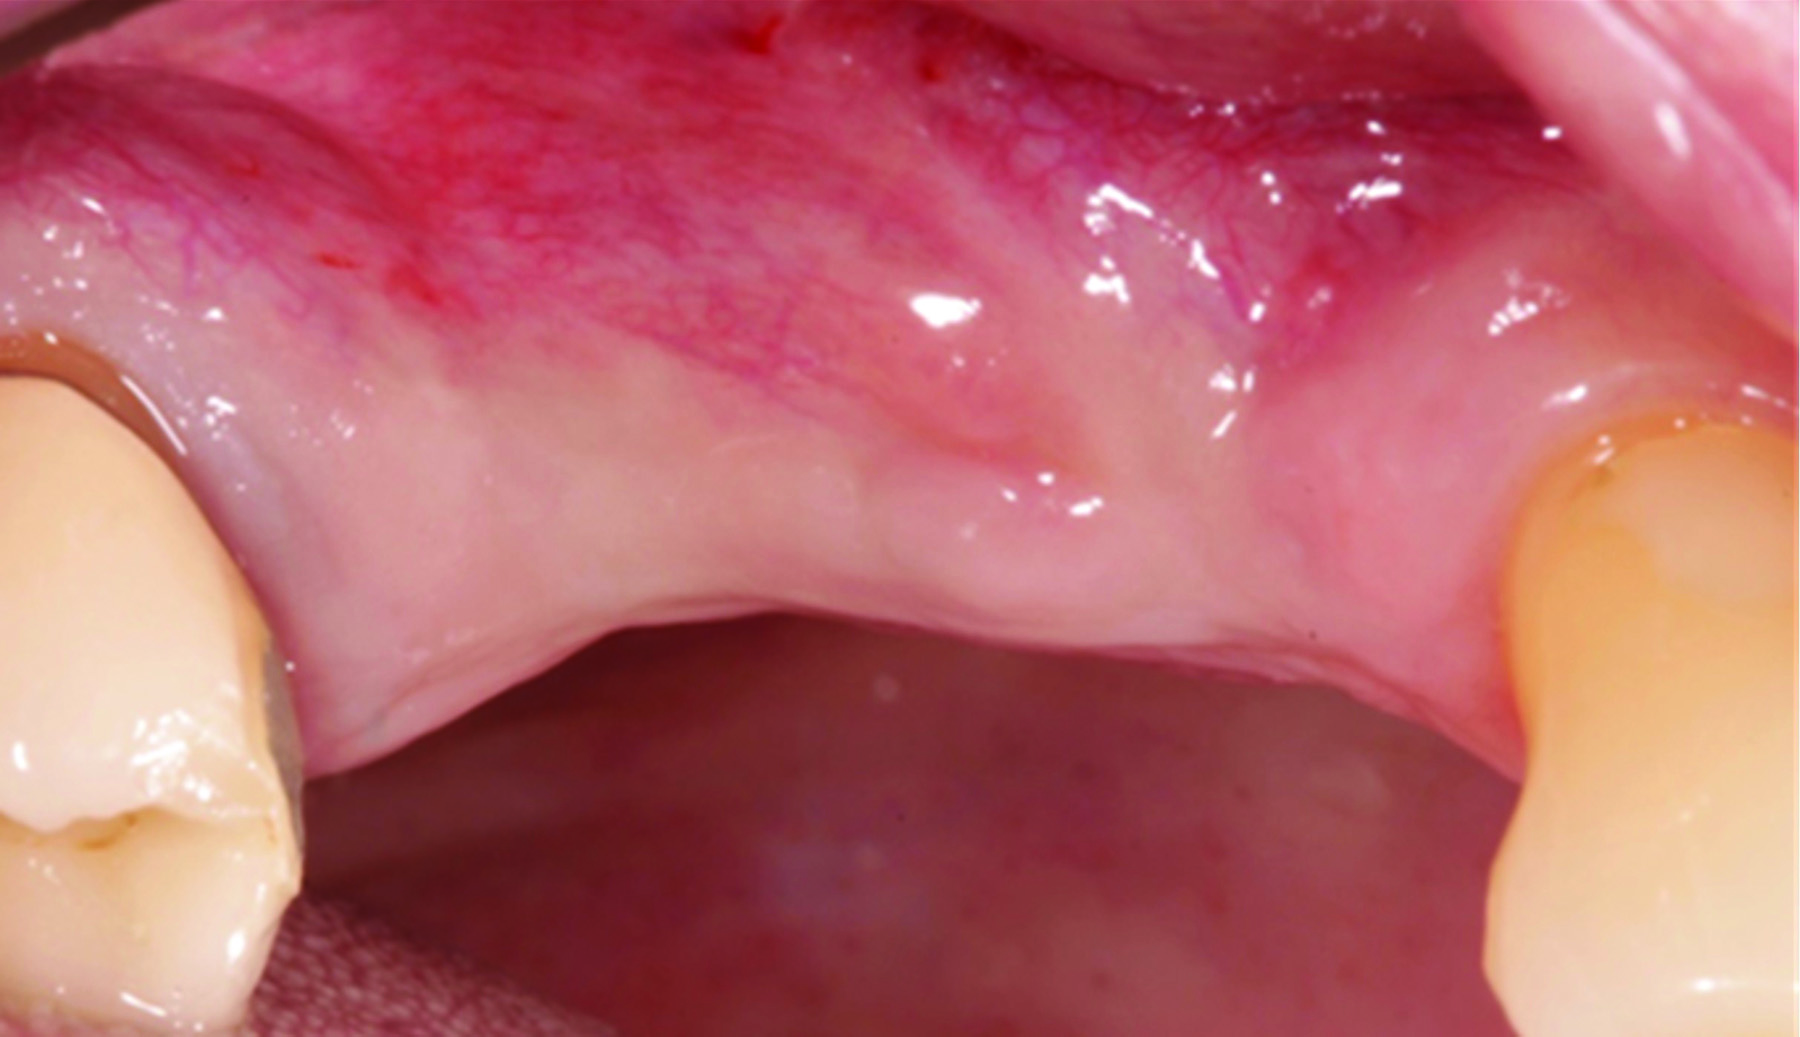

A deficient dimension of keratinized mucosa width (KMW) around dental implants is often related to patient discomfort during oral hygiene (Figure 1). Literature suggests the dimension of KMW should be considered as a risk factor for peri-implant mucositis and peri-implantitis.1-4 KMW is also associated with patient satisfaction regarding implant esthetics. Mucosal thickness (MT) is crucial for both esthetic outcomes and peri-implant health.5-7 Thicker mucosal tissue provides stability for the mucosal margin, which leads to less risk of mucosal recession. This underscores the importance of considering tissue thickness in implant planning and restoration.

KMW is the dimension of keratinized soft tissue extending from the mucosal margin to the mucogingival junction (MGJ) in the apicocoronal direction. KMW is the coronal component of the peri-implant soft tissues, and beyond these tissues apically is the non-keratinized alveolar mucosa (Figure 1 through Figure 3). Where KMW is absent in certain conditions, there is solely non-keratinized peri-implant mucosa adaptation to the implant prosthesis. KMW is measured clinically with an instrument such as a periodontal probe in the apicocoronal direction, or an estimate of KMW can be made based on photographs. While as a clinical guideline or for research purposes it has been proposed that at least 2 mm of KMW be present, this amount is still debated as to whether or not it is necessary.8

MT is the horizontal dimension of the peri-implant soft tissue and may or may not be keratinized. MT is an important aspect of implant esthetic outcomes, especially at the most coronal aspect around the implant restoration. Around thin mucosa the color of the underlying restoration material may show through and result in esthetic deficiencies (Figure 1). Conversely, thick tissue can minimize the shading effect of underlying restoration materials and may compensate for any bony dehiscence around the implant body. In a systematic review, it was reported that after soft-tissue augmentation was conducted to increase MT, less interproximal marginal bone loss resulted around the implant.9

Fig 1. The peri-implant mucosa of implant No. 19 presents erythema with a lack of KMW. The dark color of the underlying restoration is showing through the thin peri-implant mucosa. The dotted line indicates the MGJ. The distance from the margin of the peri-implant mucosa to the MGJ is the KMW.

Figure 1